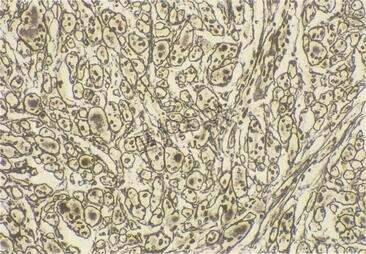

网织纤维染色(银染)

是指在疏松结缔组织 中含量较少,纤维较细,有分支,彼此交织成网状。 用浸银法可将纤维染成黑色,故又称嗜银纤维(argyrophilic fiber)。